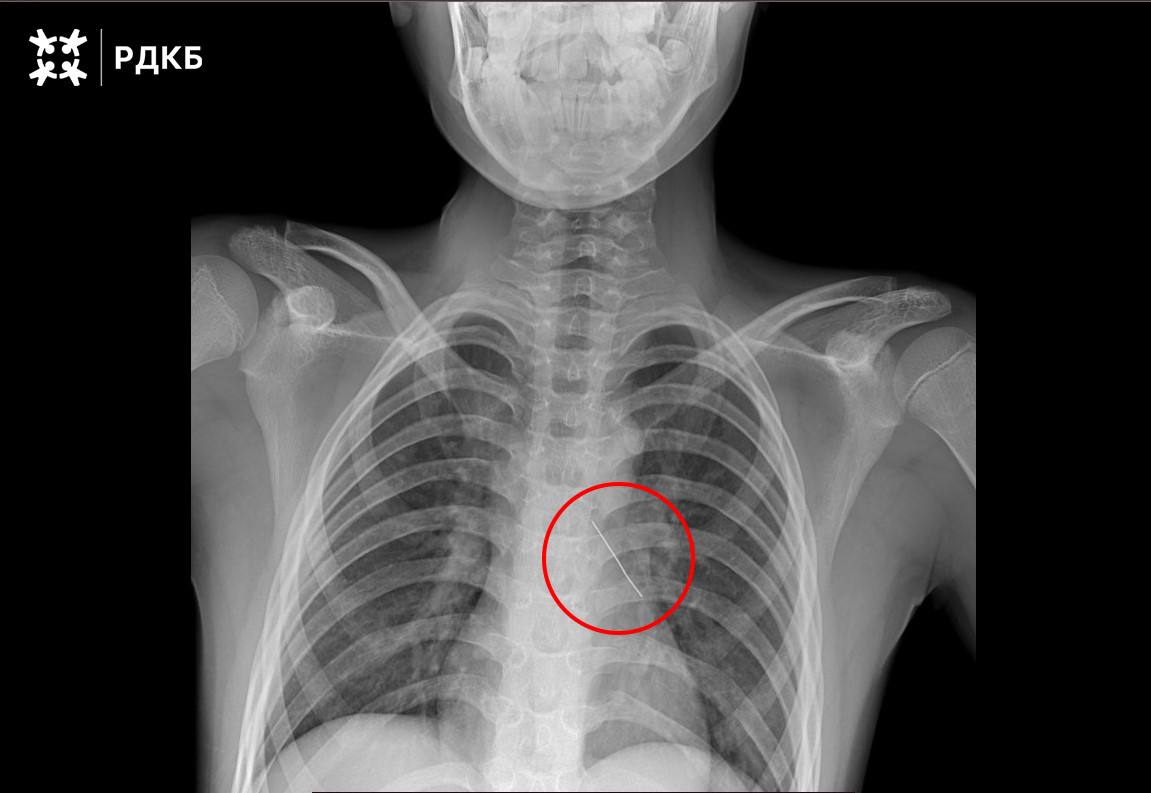

При поступлении в РДКБ мальчик мог говорить только шёпотом и испытывал сильные боли в груди. С помощью рентгенологического исследования специалисты установили, что булавка находится в области нижней доли левого бронха.

В ходе малоинвазивного вмешательства мы завели эндоскоп в левый главный бронх ребёнка, а при осмотре его нижней доли обнаружили скопление мокроты. После её удаления визуализировали предмет округлой формы — колпачок французской булавки. Инородное тело было изогнуто и острым концом пронзило бронх пациента. Такая травма может привести к попаданию свободного воздуха в плевральную полость, дальнейшим нарушениям дыхания, к сдавлению и даже коллапсу лёгкого, — рассказал заведующий отделением реконструктивной и восстановительной хирургии грудной полости РДКБ Евгений Андреев.

Специалисты под визуальным контролем аккуратно извлекли булавку за колпачок с помощью оптических щипцов. Это позволило минимизировать кровотечение, которое купировалось самостоятельно. После удаления острого предмета выполнили контрольную рентгенографию — в грудной полости отсутствовал свободный воздух, что подтвердило успех вмешательства.